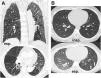

La TC torácica en espiración es una técnica complementaria de la inspiración que aporta valiosa información fisiológica y puede ser más sensible que las pruebas de función respiratoria para detectar atrapamiento aéreo. Tiene múltiples indicaciones, entre las más frecuentes están la enfermedad obstructiva de la vía aérea producida por bronquiolitis obliterante, asma, síndrome de Swyer-James, traqueomalacia, neumonitis por hipersensibilidad o sarcoidosis. En alguna de ellas, como la bronquiolitis obliterante, la TC espiratoria puede ser la única técnica de imagen que detecta alteraciones en las fases iniciales. Si queremos que sea de utilidad diagnóstica, hay que asegurarse de que el estudio tenga calidad suficiente. Para ello se recomienda explicar al paciente en qué consiste la prueba, emplear instrucciones precisas y realizar un breve entrenamiento antes de iniciar la adquisición. En este trabajo sugerimos estrategias para optimizar la técnica y proponemos un algoritmo para interpretar los hallazgos radiológicos en el contexto de la patología obstructiva pulmonar.

Expiratory CT scan is a complementary technique of inspiratory CT that provide valuable physiological information and may be more sensitive to detect air trapping than pulmonary function tests. It is useful in many obstructive airway diseases, including obliterative bronchiolitis, asthma, Swyer-James syndrome, tracheomalacia, hypersensitivity pneumonitis and sarcoidosis. In obliterative bronchiolitis, expiratory CT scan may be the only imaging technique that shows abnormalities in the early phase of disease. In order to obtain a good quality study, we should explain the procedure to the patient, use precise instructions and do some practice before image acquisition. Here we describe strategies to optimize the technique and propose an algorithm that help in interpretation of imaging findings in patients with obstructive airway disease.